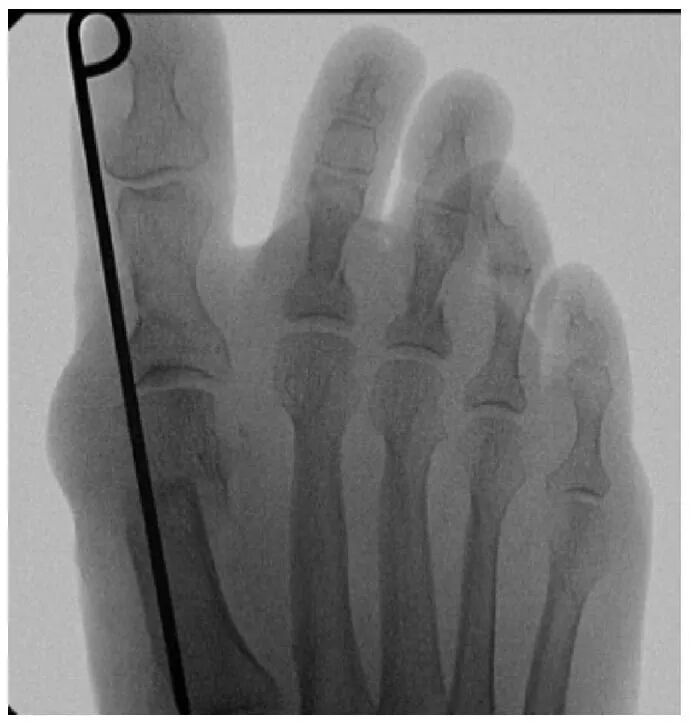

截骨完成后,将弯曲的骨膜剥离器插入截骨部位,以平移第一跖骨头。通过近节趾骨基部内侧的3毫米切口进行额外的Akin截骨术。使用一枚2毫米克氏针通过截骨端沿拇趾内侧软组织向远端穿过,从趾尖的跖内侧穿出。然后将克氏针逆行插入第一跖骨的髓管。

在最终确认拇外翻矫形满意后关闭伤口。应用绷带保护手术伤口和克氏针。术后一天允许患者根据耐受情况完全负重,使用前足减压的术后鞋。六周后患者可以根据耐受情况开始穿常规鞋履。